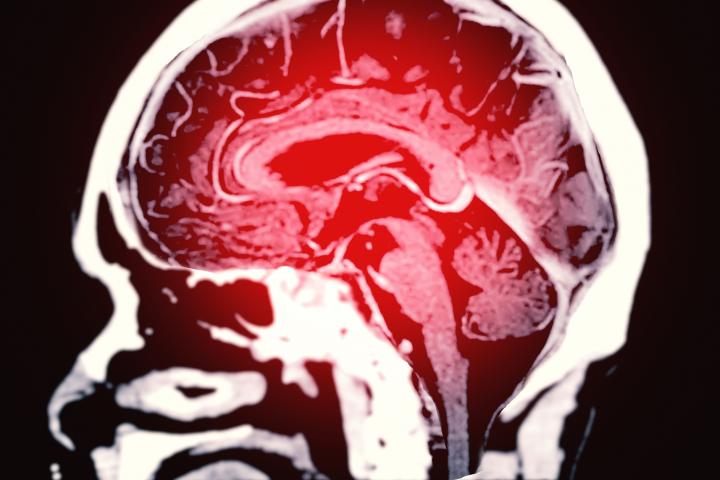

Aviso urgente de un cardiólogo tras revelar la comida que puede desembocar en un ictus

El portal web Top Santé ha recogido un estudio en el que se habla de la repercusión de cierto componente en la proteína animal que podría desencadenar una serie de procesos en el organismo que terminarían en un ictus. Se trata de la leucina, que es un tipo de aminoácido abundante.

Este compuesto, según ha relatado el sitio web ya citado, activa la mTOR. Esta es una señal biológica que la leucina tendría la capacidad de activar. Esa señal es partícipe en los procesos de crecimiento celular.

Entonces, el portal ha hablado de los macrófagos. Estos son un tipo de glóbulo blanco que se encuentra rodeando a los microorganismos y consigue destruirlos. Cuando esa señal que activa la leucina se sobreactiva en los macrófagos, así como en las células inmunes se estaría promoviendo que se formen placas ateroscleróticas.

El proceso que han explicado desde Top Santé continúa con que estas placas poco a poco se van acumulando en las arterias dificultado, por tanto, la circulación de la sangre. Es entonces cuando se podrían bloquear y llegar a desencadenar un ictus.